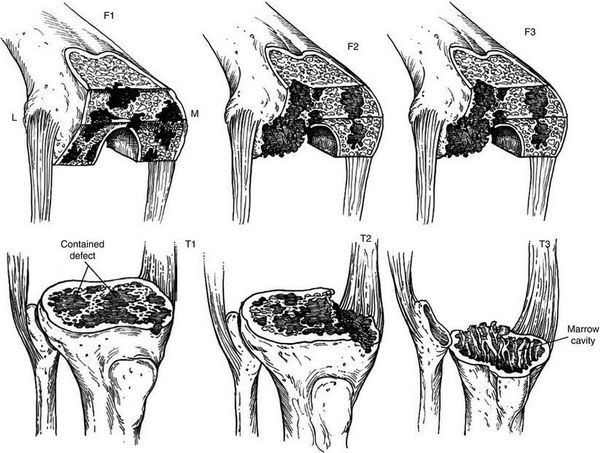

В своїй роботі ми класифікацією кісткових дефектів ложе нестабільнокористувалисяго протеза колінного суглоба за AORI (Anderson Orthopaedic Research Institute, USA), 1997 де автори виділяють 3 типа кісткових дефектів

Тип 1 – інтактна кістка (intact metaphysealbone) – невеликі кісткові дефекти, зазвичай без пошкодження кортикальної кістки. Характеризується нормальною кісткової структурою і збереженням губчастої і кортикальної кістки метафиза, нормальним рівнем суглобової лінії. позначаються як F1 – для стегнової кістки і Т1 – для великогомілкової.

Тип 2 – пошкоджена кістка (damаged metaphyseal bone) – характеризується втратою губчастої і кортикальної кісткової маси метаепіфізів, без заповнення якої неможливе створення надійної опори для компонентів ревізійного імплантату і відновлення анатомічного рівня суглобової лінії. (F2 А та F2 Б – для стегнової і Т2 А та Т2 Б – для великогомілкової кісток)

Тип 3 – дефіцит кістки (deficient metaphyseal segment) – характеризується вираженою втратою губчастої і кортикальної кісткової маси метаепіфіза, без компенсації якої неможливе створення опори для компонентів ревізіційного імплантату і відновлення нормального рівня суглобової лінії. Дефекти частіше поширюються до надвиростків і вище на стегнової кістці або до горбистості і нижче на великогомілковій кістці. (F3 А та F3 Б – для стегнової і Т3 А та Т3 Б– для великогомілкової кісток)